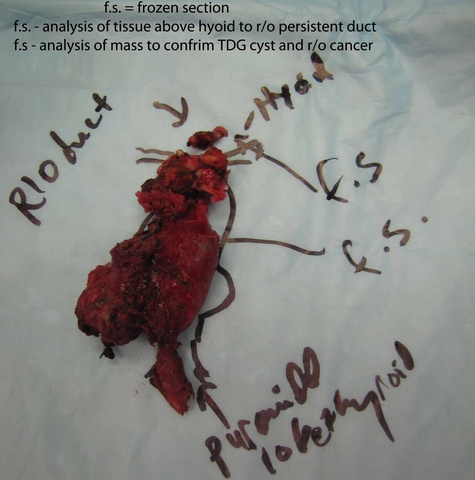

Frozen section was taken from the superior most part of the tract - revealing no evidence of a tract. Had there been a tract identified, further dissection (potentially communicating intraorally) would have been done where the hemoclips had been placed above the hyoid (see also: Case example thyroglossal duct cyst with tract through to oropharynx.)